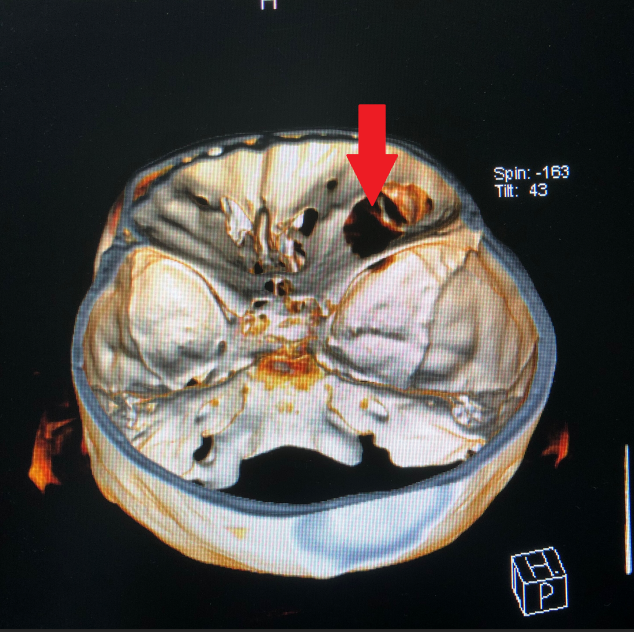

成人导航 神经外科团队接诊后对患者进行了全面检查,诊断为右眼眶肿瘤。因患者肿瘤向颅内生长,颅底及眼眶骨质已完全破坏,传统的手术方式不仅创伤大,更可能因为颅底结构无法完全重建导致患者脑脊液漏,引起颅内感染。神经外科联合眼科进行了手术方式的讨论,根据术中可能出现的各种情况其制定了详细的治疗方案,认真完善术前准备后,于2018年12月24日成功为其开展“完整切除颅内外沟通瘤并颅底眼眶重建修复手术”,手术过程非常顺利,术后患者无视神经损伤,视力较术前明显改善。目前患者已康复出院。

颅底眼眶疾病是神经外科与眼科的交叉区域,我科该手术的成功开展,不仅标志着我科对眼眶骨折修复及颅底眼眶肿瘤手术新领域的开拓,也将为眼眶疾病的患者带来福音。